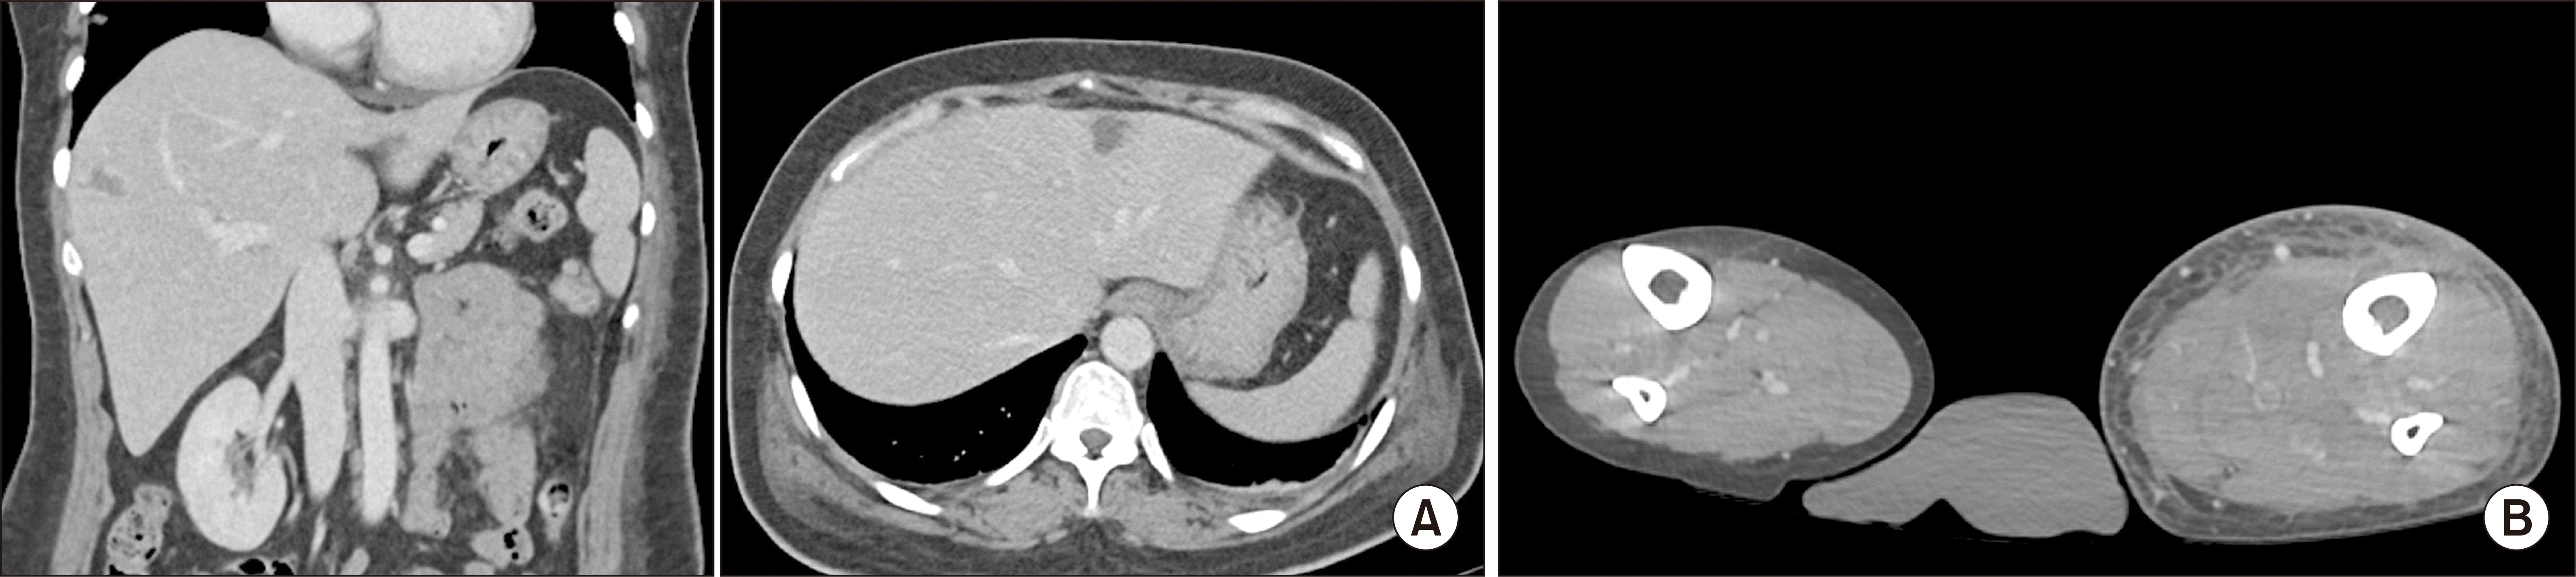

Figure 1

(A) The abdominal pelvic computed tomography (CT) shows multiple liver abscesses. (B) CT venography shows multifocal thromboses affecting left calf deep veins.